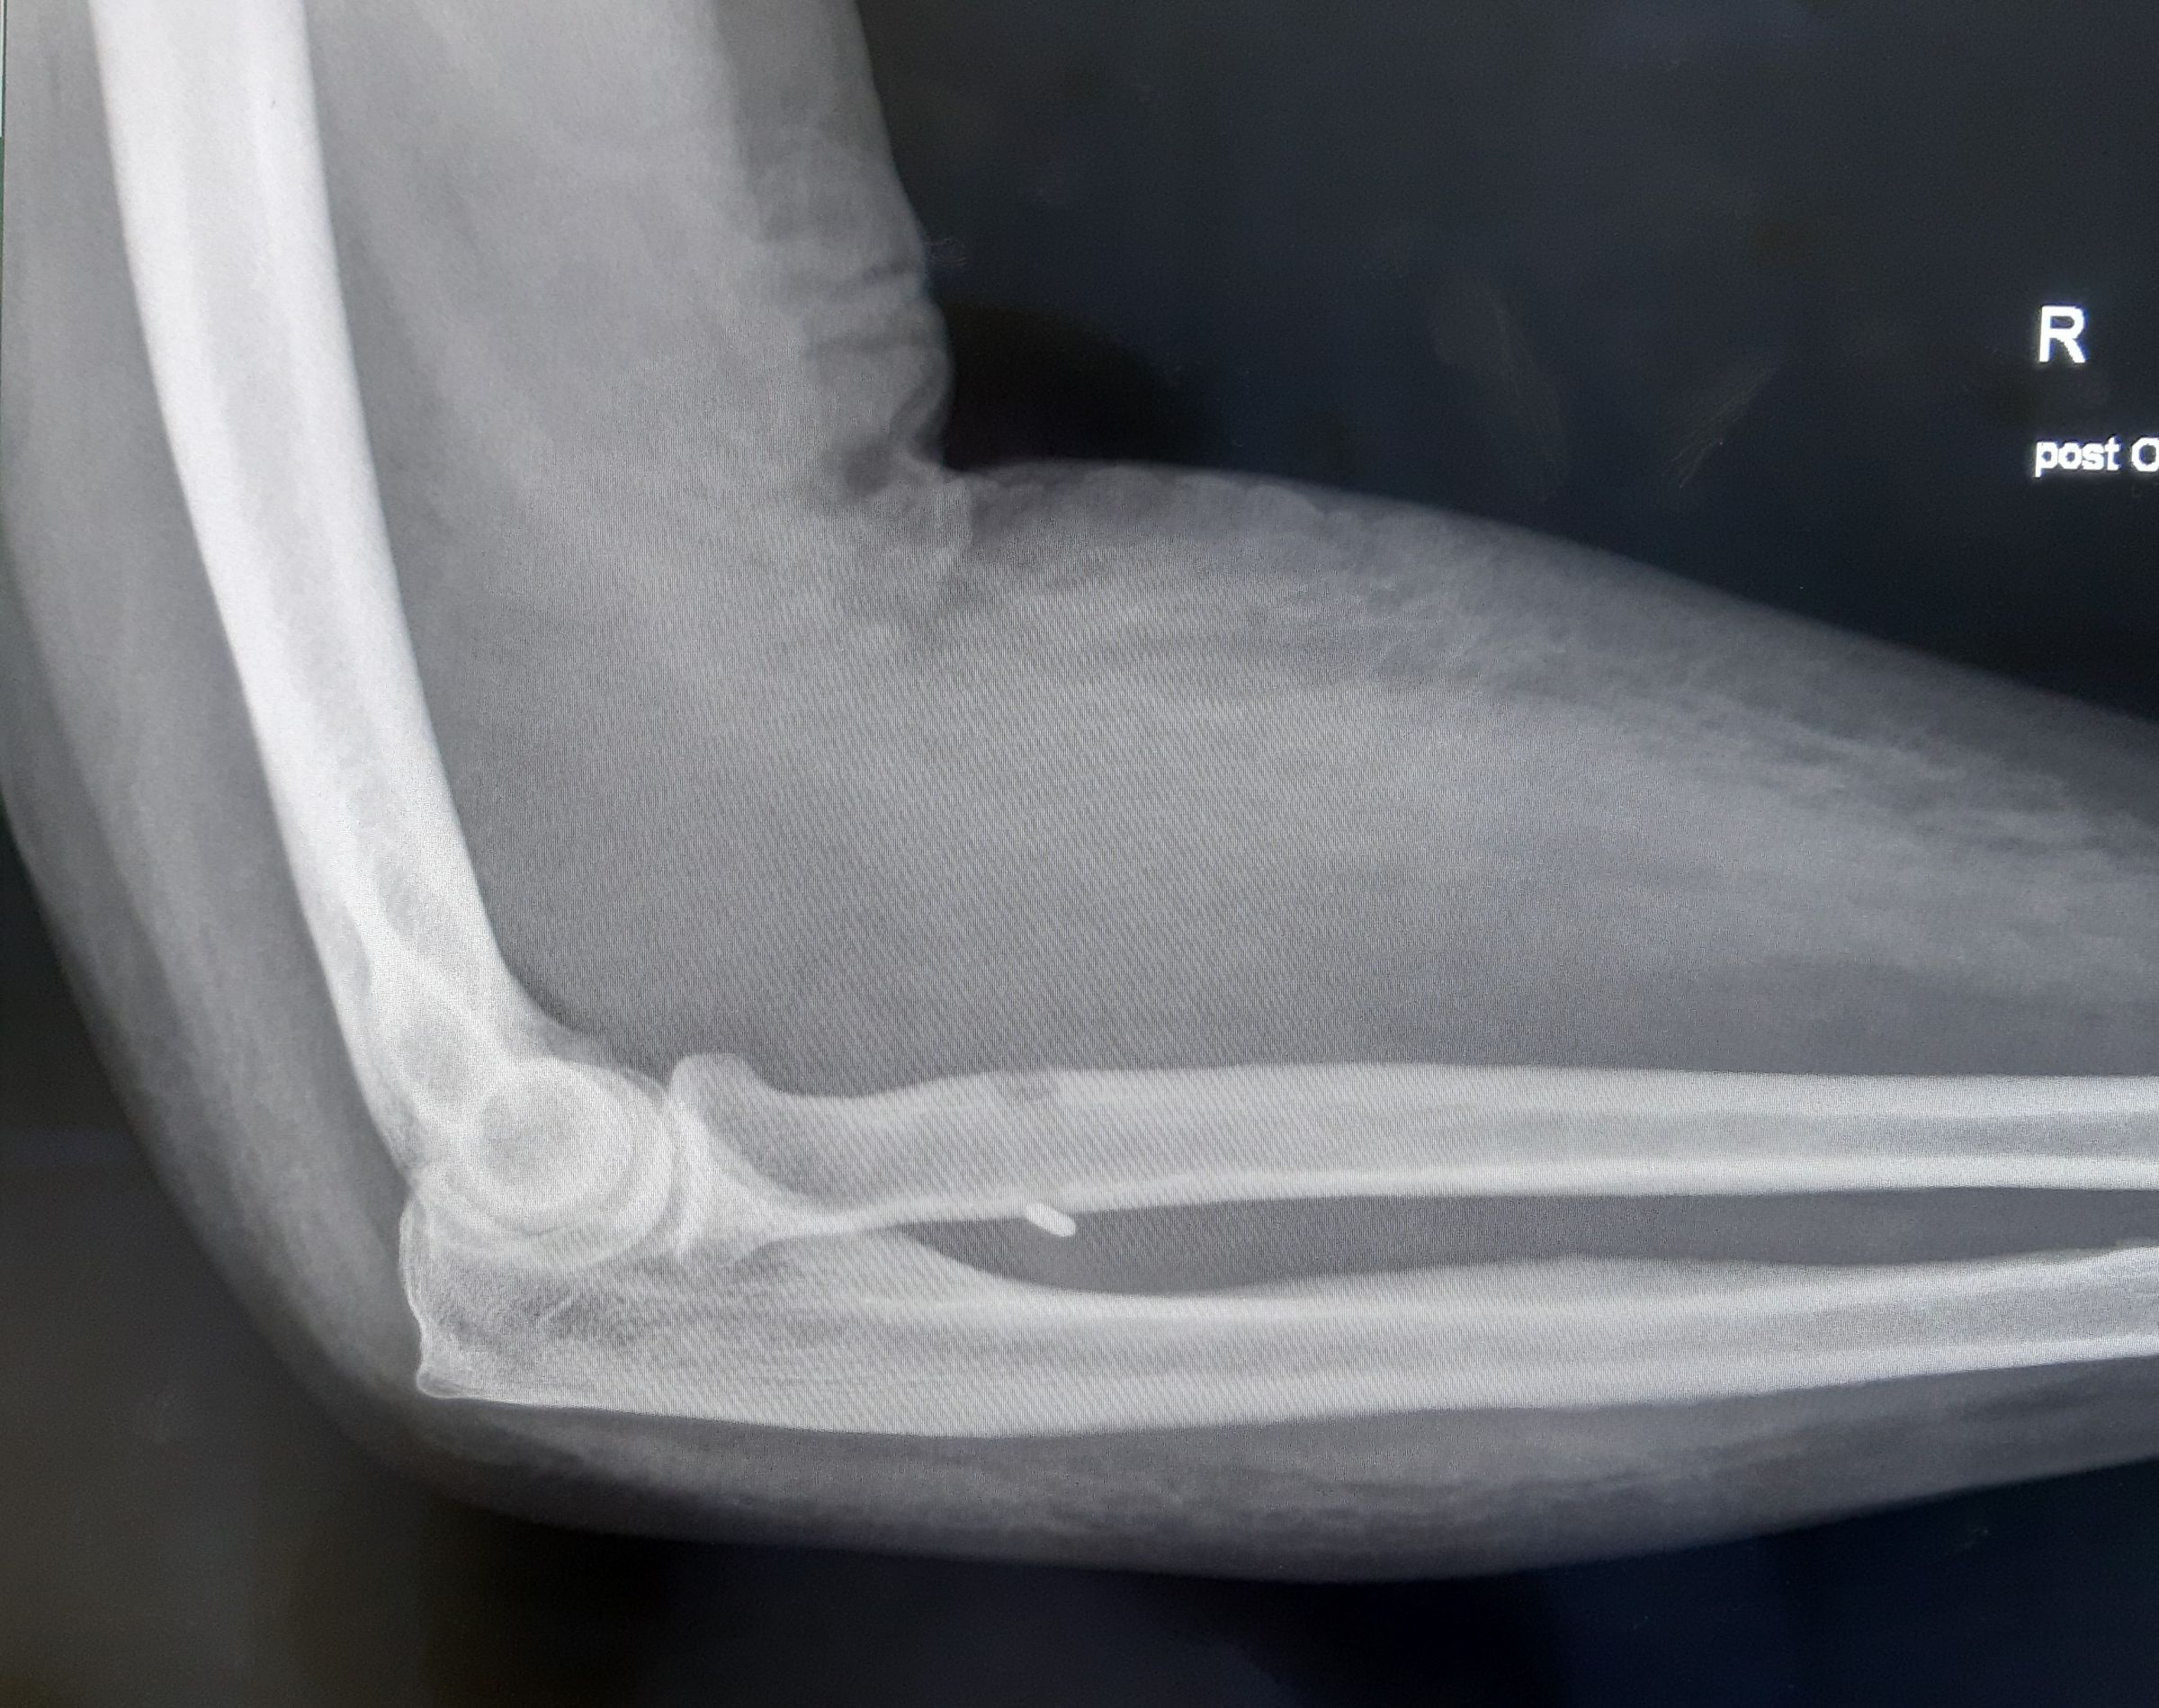

RISS DER DISTALEN BIZEPSSEHNE

Definition

Ein Sehnenriss entsteht, wenn eine Kraft plötzlich auf den angespannten Muskel einwirkt. Meist gehen degenerative Veränderungen der Sehne voraus, die durch starke Beanspruchungen entstehen und meist unbemerkt bleiben. Fast immer sind Männer im mittleren Lebensalter betroffen, die relativ muskelkräftig sind und manuell arbeiten oder Muskelaufbau betreiben.

Klinik und Diagnose

Meist wird vom Patienten ein „schnalzendes“ Geräusch vernommen, in der Ellenbeuge kommt es zu Schmerzen und es bildet sich eine Hämatomverfärbung. Im weiteren Verlauf kommt es zu einem „nach-oben-Wandern“ des Muskelbauches.

Prinzipiell handelt es sich um eine klinische Diagnose. Bei einem Riss der Sehne ist in der Ellenbeuge anstelle der Sehne eine Delle tastbar. Wenn die Verletzung schon einige Tage alt ist, ist der Muskelbauch bereits nach oben gewandert. Zur Sicherung der Diagnose sollte jedoch eine Ultraschalluntersuchung oder eine Magnetresonanztomographie durchgeführt werden.

Therapie

Da durch den Riss der ellenbogennahen Bizepssehne eine Minderung der Beugekraft im Ellenbogengelenk um 30-40%, sowie ein Kraftverlust bei Auswärtsdrehen des Unterarmes von ungefähr 50% resultieren, sollte vor allem bei beruflich und sportlich aktiven Patienten ein operatives Vorgehen empfohlen werden.